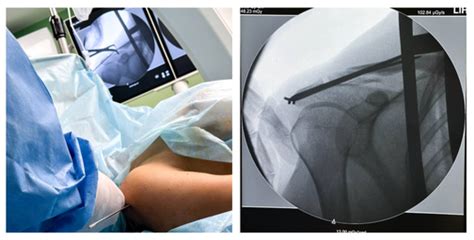

Повреждения шеи - Хирургия